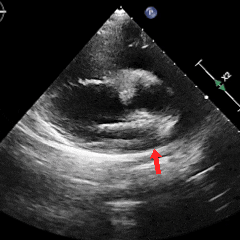

经胸右心声学造影:经左肘静脉注入震荡生理盐水(8mL生理盐水+1mL回抽静脉血+1mL空气经震荡制成),上腔、右房依次显影,造影剂完全充盈右心后,平静呼吸时,左房内即可探及微泡回声,约20-30个/切面/帧;瓦氏呼吸释放即刻,左房内探及微泡回声,不可计数。

术前瓦氏动作后经胸右心声学造影(大量)